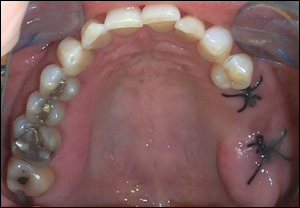

Fig 2: After considerable thought, the treatment plan was to extract the mobile molar and the healthy bicuspid and insert a 3-unit fixed bridge supported by two dental implants. This case was engineered to provide a solid anterior implant of average size in good quality bone and a solid posterior implant of above average size. This photo demonstrates the extraction sites.